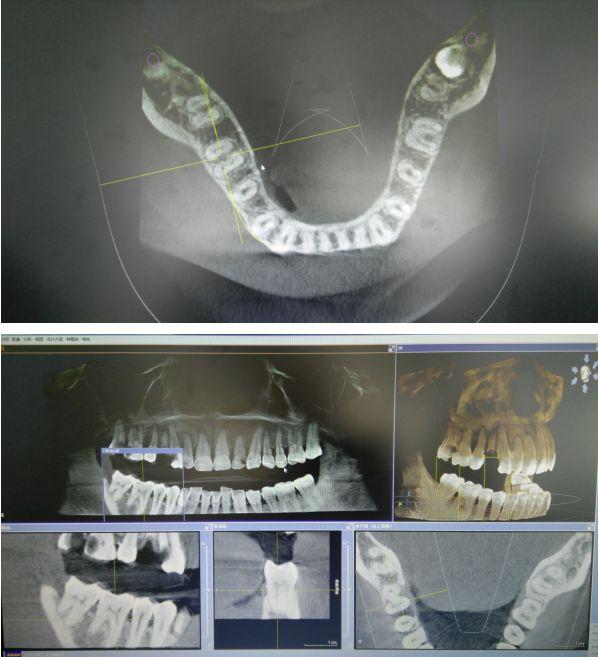

CBCT掃描可準確分析頜骨植入區(qū)的骨質、骨量、骨密度及植體與下頜神經管、上頜竇的關系,臨床醫(yī)生可以在圖像上模擬種植,直接與患者進行溝通及交流,并可指導手術者在手術方案中避開危險區(qū)域,手術的性。此外,臨床醫(yī)生還可以利用CT數據進行數字模型重建,配合軟件預先做好手術模板使種植手術更快捷。